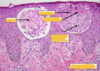

bullous pemphigoid

elderly pts

tense blisters and vesicles

lower abd, thighs, FAs

10-30% involve mucosa

severe pruritis

negativec nikolky sign

rx. topical / systemic CTSDs

Elderly, tense blisters and vesicles

lower abd, thighs, FAs

severe pruritis

negative nikolsky sign

elderly, tense blisters, vesicles

severe pruritis

negative niklosky sign